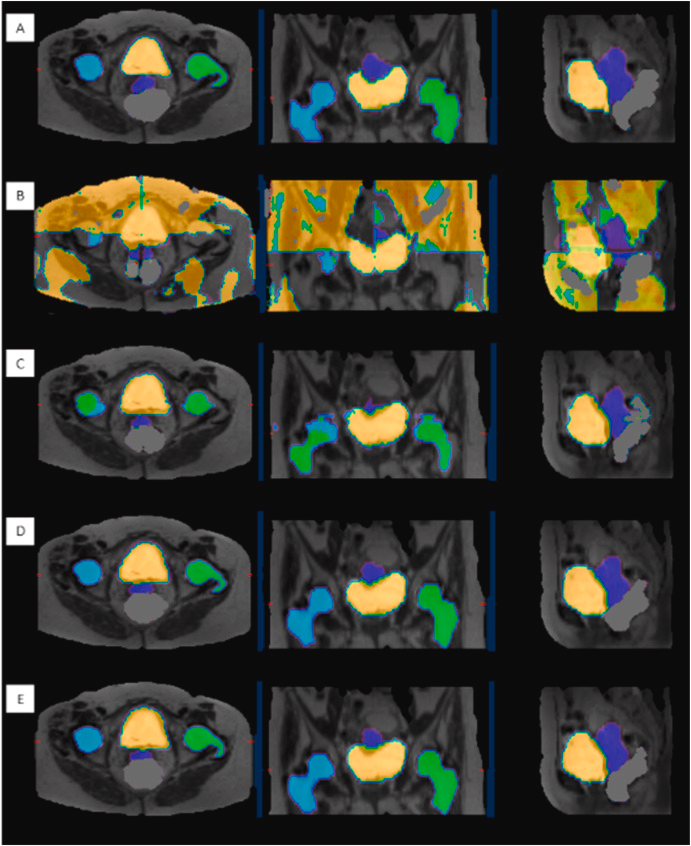

Contouring automatizzato del volume tumorale: il contouring manuale, descritto come “indaginoso, laborioso, time consuming, operatore dipendente”, viene trasformato dall’AI. I tempi si riducono drasticamente, passando da 2 ore a 20 minuti, fino a 2 minuti per paziente. Questo non solo genera un enorme guadagno di efficienza, ma introduce un livello di oggettività senza precedenti, permettendo di identificare, misurare e confrontare le lesioni nel tempo per una valutazione più accurata della risposta alla terapia.

L’utilità del contouring basato su AI (come le reti U-Net) risiede in un paradosso apparente: il suo successo si misura proprio dalla sua indistinguibilità dal lavoro manuale.

Quando addestriamo questi algoritmi, utilizziamo come ‘Gold Standard’ i contorni tracciati da medici esperti. L’AI impara a replicare quelle stesse curve, includendo correttamente il GTV (volume tumorale) e risparmiando gli organi a rischio (OAR), esattamente come farebbe un operatore umano.

Dal punto di vista qualitativo, quindi, non cambia molto: il risultato finale è clinicamente sovrapponibile. La rivoluzione è nel flusso di lavoro. Il contouring manuale è un compito ripetitivo, ‘time-consuming’ e soggetto a stanchezza. L’AI trasforma il ruolo del medico nucleare o del radioterapista: non più ‘disegnatore’ che parte da un foglio bianco, ma ‘supervisore’ che valida un lavoro già fatto.

L’AI fornisce una bozza ad alta fedeltà. Se la differenza geometrica è minima, il guadagno in termini di tempo e la standardizzazione del metodo (riducendo la variabilità inter-operatore) rappresentano il vero valore aggiunto per il sistema sanitario.